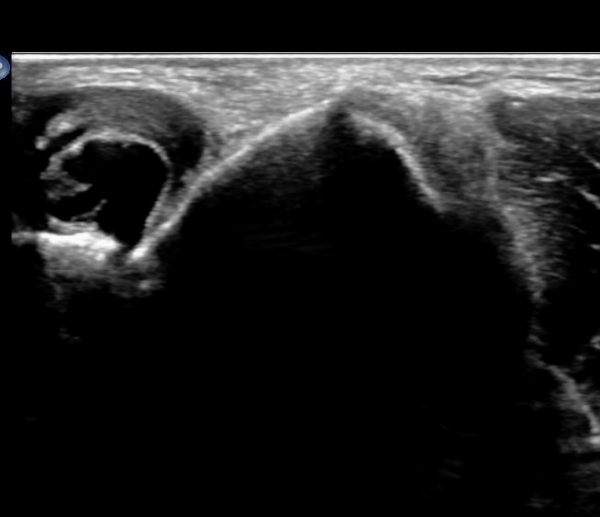

ÆÈ²ÞÄ¡ ¾ÕÂÊ ¿ÜÃø, ¼ÒµÎ(capitulum) Á¾´Ü¸é°Ë»ç¿¡¼­ ¼ÒµÎ Àü¸éºÎ¿Í ¿ä°ñµÎ Àü¸é¿¡ ¼ö¾×Àú·ù°¡ °üÂûµÊ(»çÁø 3, 4).

¼ÒµÎ Ⱦ´Ü¸é°Ë»ç¿¡¼­µµ ¼ÒµÎ Àü¸é¿¡ ¼ö¾×Àú·ù°¡ °üÂûµÊ(»çÁø 5).